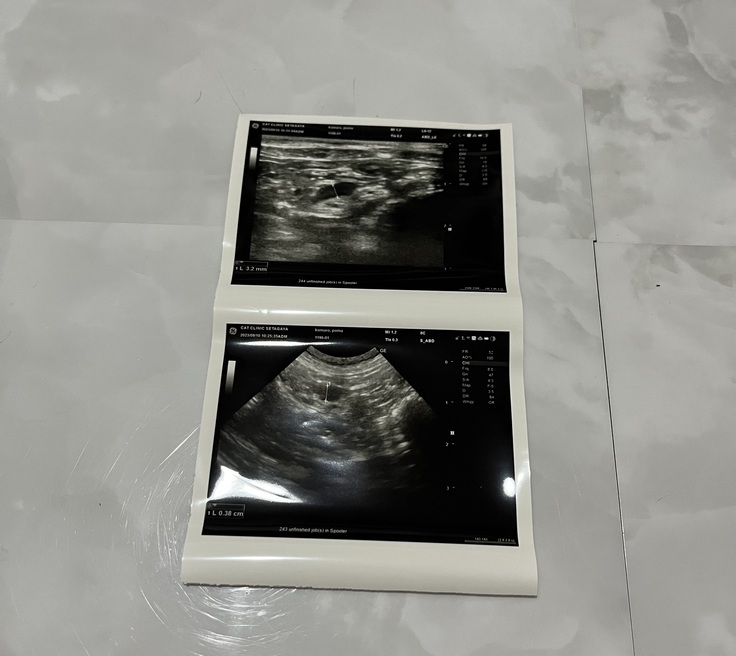

2度目の投薬を無事に終え、9月10日に1ヶ月検診に行ってきましたのでご報告いたします。

結果は、炎症マーカーや血液検査の数値は良好で、エコーでリンパの様子をみても正常範囲内とのことで、再発はしていないとのことでした。